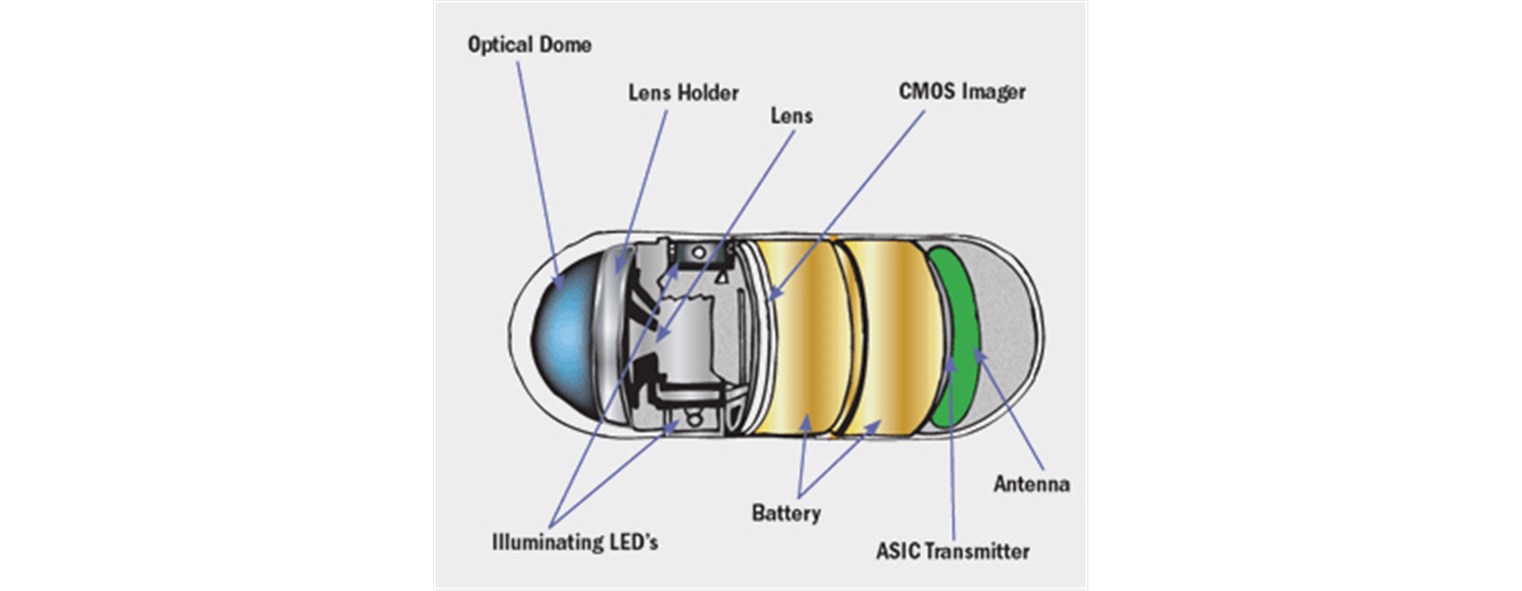

הקפסולה הינה גלולה גדולה ( 32X11 מ"מ) ובמשקל זעיר של 4 גרם. גוף הקפסולה מורכב

ממצלמה (בדגמים מסוימים 2 מצלמות), משדר זעיר וסוללה שמספיקה לכ-12 שעות עבודה.

הקפסולה נבלעת על ידי הנבדק וממשיכה במסעה לאורך מערכת העיכול בעזרת התנועתיות הטבעית של המעי, ונפלטת מהגוף באופן טבעי. תוך כדי המסע הגלולה מצלמת 2-6 תמונות ברזולוציה גבוהה ובזווית רחבה בכל שנייה.

התמונות משודרות באופן אלחוטי למשדר קטן המחובר לגופו של הנבדק. אין צורך בגלולה עצמה כדי לקרוא את התמונות היות והן נשמרות על גבי המשדר בזמן אמת. את המשדר מחזירים כעבור 12 שעות או למחרת למכון הגסטרו, שם הוא מתחבר לעמדת מחשב בה מתבצע תהליך הורדת התמונות. התמונות נערכות על ידי תוכנת הפיענוח לסרט שנצפה לאחר מכן על ידי הרופא.